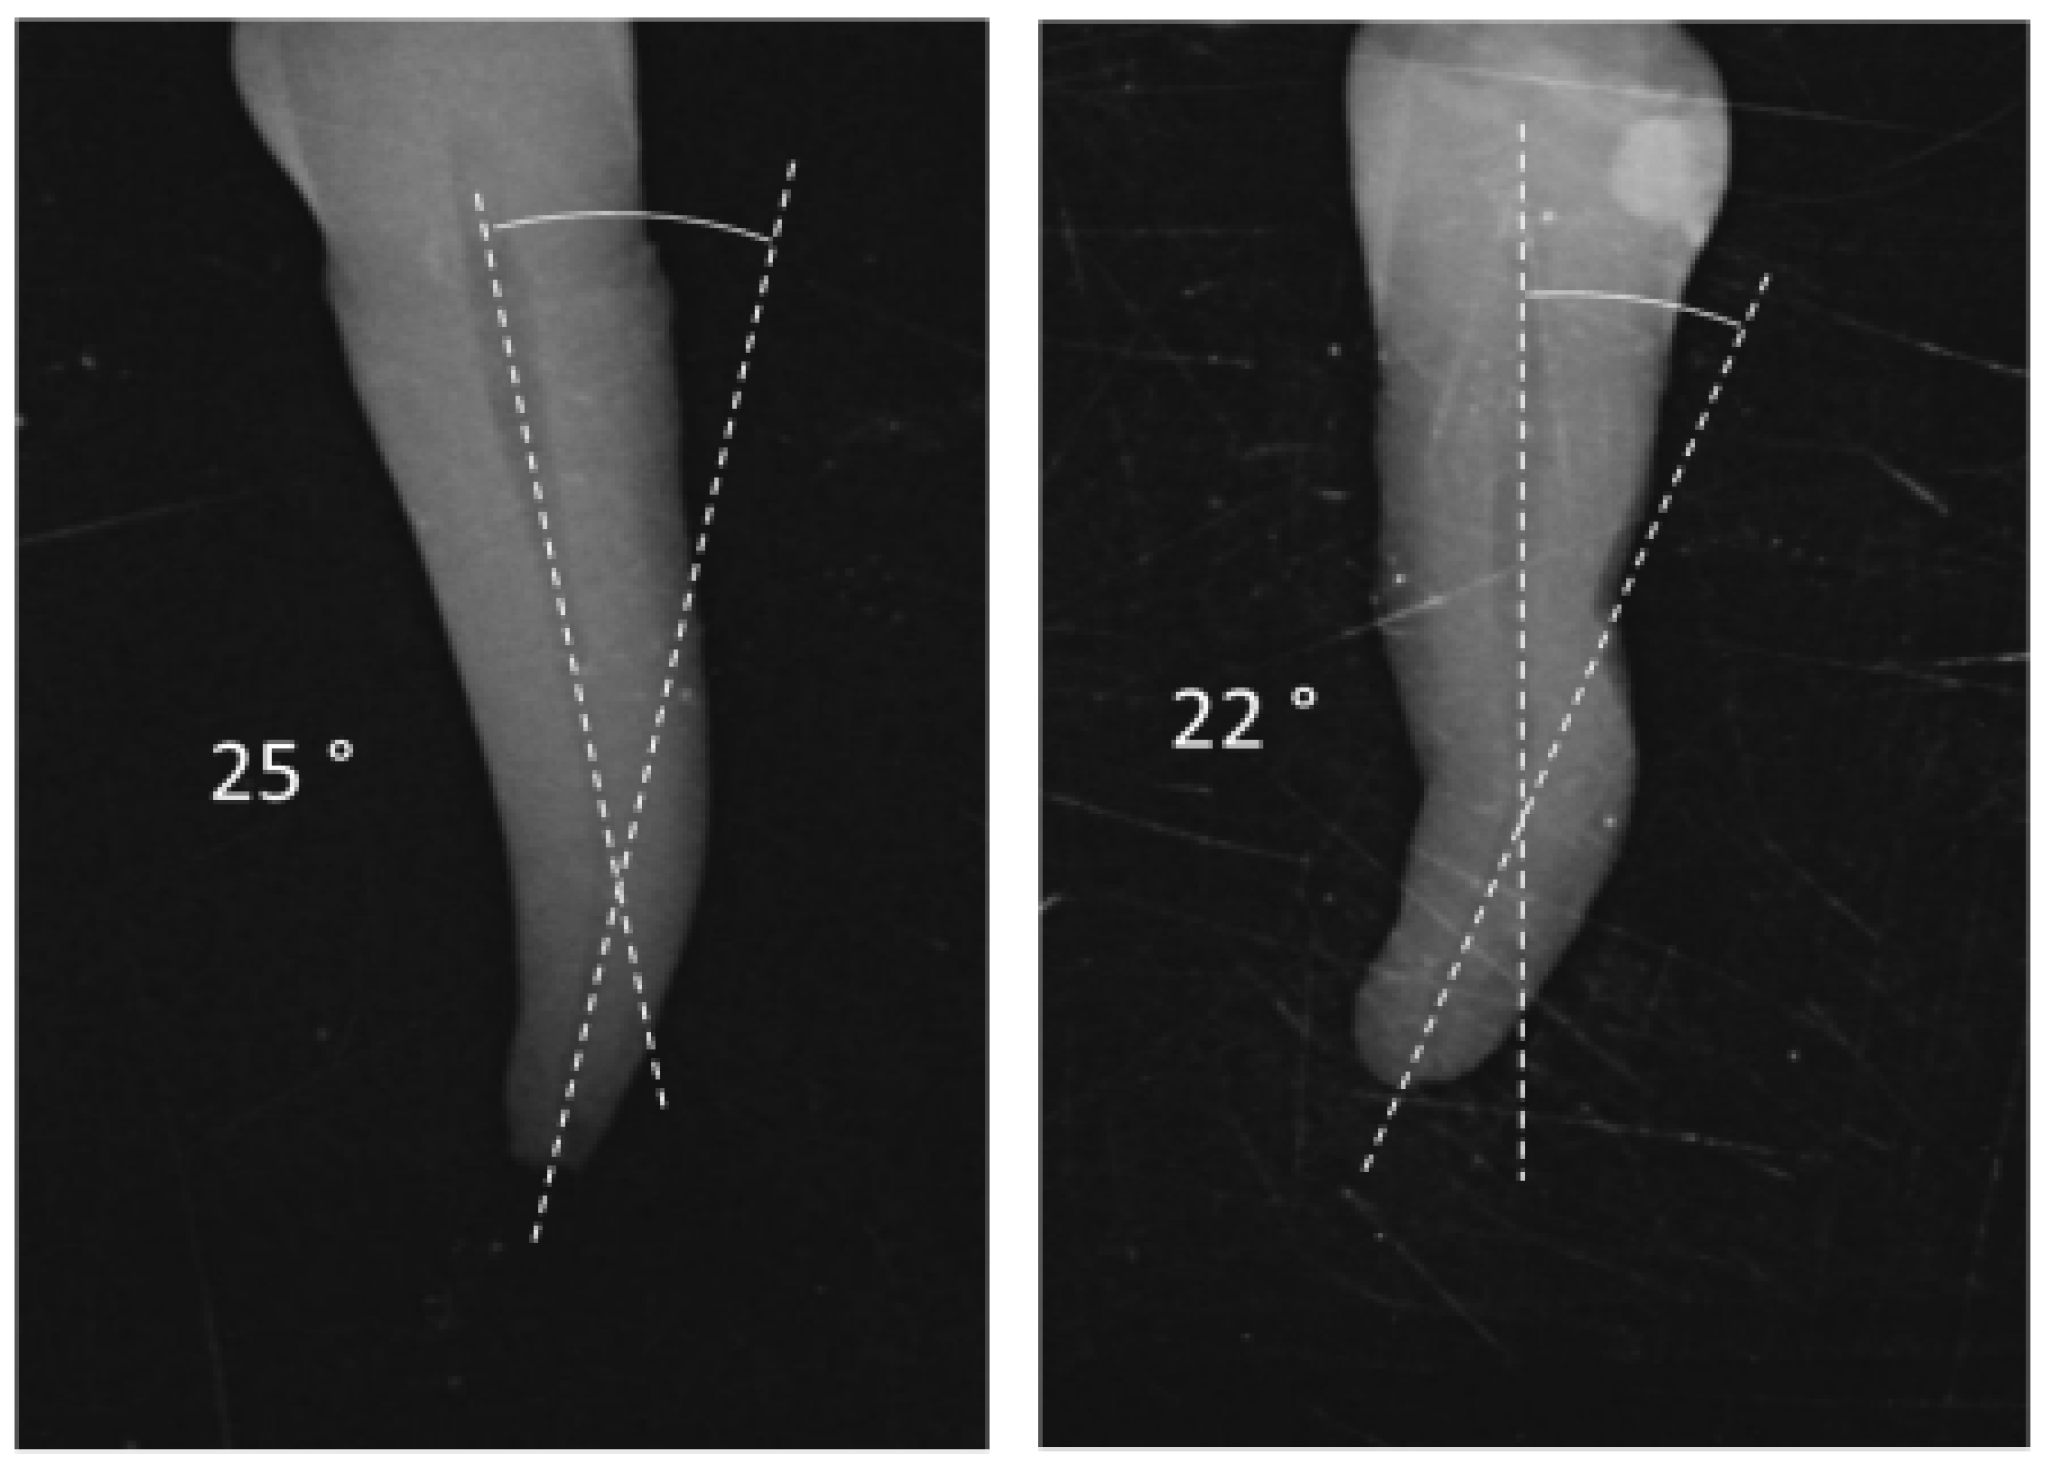

- Schneider, S.W. A comparison of canal preparations in straight and curved root canals. Oral Surg. Oral Med. Oral Pathol. 1971, 32, 271–275. [Google Scholar] [CrossRef] [PubMed]